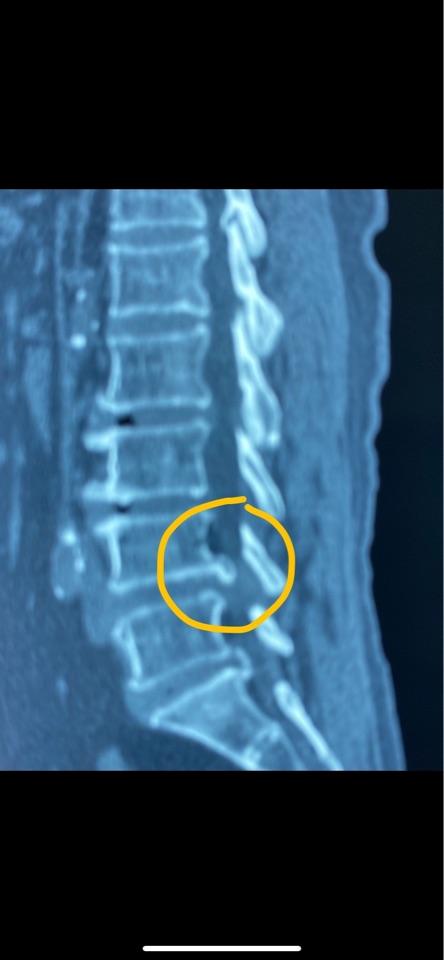

腰椎CT显示:腰4-5椎间盘突出,钙化严重,导致椎管狭窄